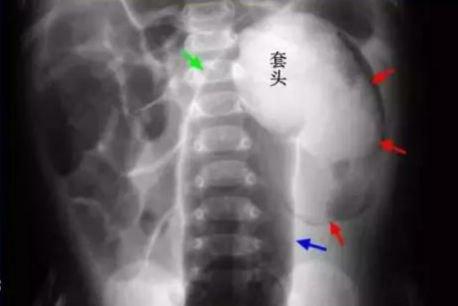

肠套叠X线腹部平片

肠套叠:是由于种种原因导致部分肠管及肠系膜套入邻近肠腔所致的一种肠梗阻,通俗的说法是一段肠管被套入另一段肠管的肠腔内,套入的肠管被卡住退不出来了。婴儿肠套叠发病率的60%,尤其是4~6月发病率最高。

腹部B超检查:可见肠套叠部位的“同心圆”或“套筒征”,就提示肠套叠诊断。